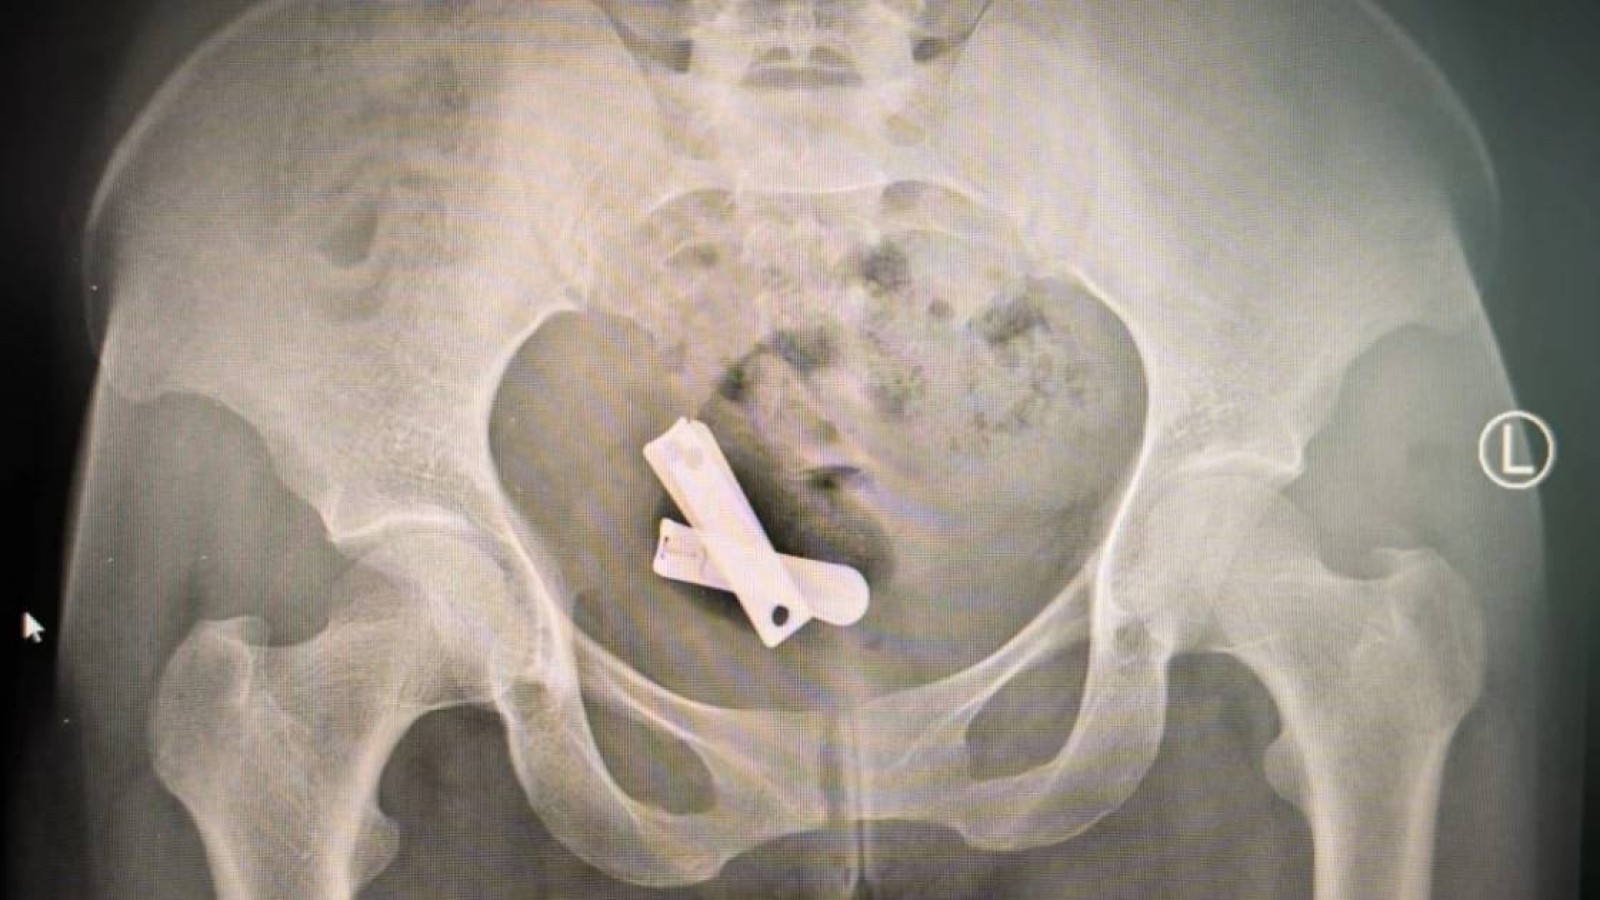

Мекелле қаласындағы Айдер ауруханасының дәрігерлері көптеген әйелдердің жатырынан тырнақ, бұранда, пластик, құм, тастар және хаттар алынғанын мәлімдеді. Бұл әрекет алғаш естігенде дәрігерлердің өзіне де психологиялық соққы болған. Бір әйелдің денесінен алынған рентген суретінде — іш қуысына дейін кіріп кеткен тырнақ пен шеге, металл заттар бейнеленген.

Бедеулікке ұшырату мақсатында жасалған шабуылдар кезінде әйелдердің жатырына, әдетте зорлықтан кейін, мынадай тырнақ кескіш секілді бөгде заттар енгізілген. Фото: Химена Борразас.